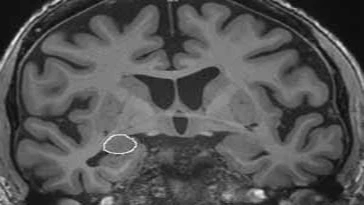

The number of friends you have can be accurately predicted by the size of a small almond-shaped part of the brain called the amygdala, according to a university study published this week. The strong correlation between a larger amygdala and a full social life holds true regardless of age or gender.

Scientists have discovered that the amygdala, deep within the temporal lobe, is important to a rich and varied social life among humans.

"We know that primates who live in larger social groups have a larger amygdala, even when controlling for overall brain size and body size," says Lisa Feldman Barrett, PhD, of the Massachusetts General Hospital (MGH) Psychiatric Neuroimaging Research Program and a Distinguished Professor of Psychology at Northeastern University, who led the study. "We considered a single primate species, humans, and found that the amygdala volume positively correlated with the size and complexity of social networks in adult humans."

The researchers also performed an exploratory analysis of all the subcortical structures within the brain and found no compelling evidence of a similar relationship between any other subcortical structure and the social life of humans. The volume of the amygdala was not related to other social variables in the life of humans, such as life support or social satisfaction.

"This link between amygdala size and social network size and complexity was observed for both older and younger individuals and for both men and women," says Bradford C. Dickerson, MD, of the MGH Department of Neurology and the Martinos Center for Biomedical Research. "This link was specific to the amygdala, because social network size and complexity were not associated with the size of other brain structures." Dickerson is an associate professor of Neurology at Harvard Medical School, and co-led the study with Dr. Barrett.

The researchers asked 58 participants to report information about the size and the complexity of their social networks by completing standard questionnaires that measured the total number of regular social contacts that each participant maintained, as well the number of different groups to which these contacts belonged. Participants, ranging in age from 19 to 83 years, also received a magnetic resonance imaging brain scan to gather information about the structure of various brain structures, including the volume of the amygdala.